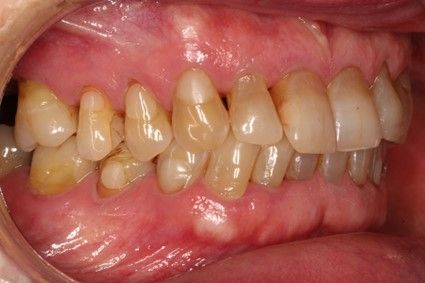

Material y método. Se ha llevado a cabo un estudio retrospectivo de pacientes tratados mediante implantes extracortos (5,5 y 6,5 mm de longitud) colocados mediante elevación transcrestal sin el uso de injerto. Como variables principales se han estudiado: la pérdida ósea crestal de los implantes y la ganancia en altura sobre el ápice. Como variable secundaria se ha estudiado la supervivencia de los implantes.

Resultados. Fueron reclutados 13 pacientes en los que se insertaron 30 implantes. Una vez insertados y cargados los implantes, la altura media final fue de 9,68 mm (+/- 2,66), lo que supone una ganancia promedio de 5 mm. A los 10 años, se observó una disminución media de la altura ósea ganada en los implantes en conjunto de 0, 29 mm (+/- 0,77). La media de la pérdida ósea mesial fue de 0,73 mm (+/- 0,75 mm) y la media de la pérdida ósea distal fue de 0,98 mm (+/- 1,2 mm). La supervivencia fue del 100%.

Material and methods. A retrospective study of patients treated with extra-short implants (5.5 and 6.5 mm in length) placed by transcrestal elevation without the use of a graft was carried out. The main variables studied were: the crestal bone loss of the implants and the gain in height above the apex. Implant survival was studied as a secondary variable.

Results.Thirteen patients were recruited and 30 implants were inserted. Once the implants were inserted and loaded, the mean final height was 9.68 mm (+/- 2.66), which represents an average gain of 5 mm. At 10 years, there was a mean decrease in the overall bone height gain of the implants of 0.29 mm (+/- 0.77). The mean mesial bone loss was 0.73 mm (+/- 0.75 mm) and the mean distal bone loss was 0.98 mm (+/- 1.2 mm). Survival was 100%.